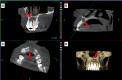

This case report highlights the successful healing of a large periapical lesion through non-surgical root canal retreatment. A 29-year-old male patient presented with a significant radiolucency associated with teeth #21 and #22, initially treated non-surgically. Despite the lesion's size, the treatment, which included thorough canal disinfection and obturation, led to substantial healing. A follow-up cone-beam computed tomography (CBCT) scan after one year confirmed the buccal cortical bone reformation and improvement in the incisive canal area except for the apical region of #21. Subsequently, root canal retreatment was performed for #21. Complete healing was achieved after two years, demonstrating that even extensive periapical lesions can be effectively treated with non-surgical endodontic retreatment, avoiding invasive surgical intervention.